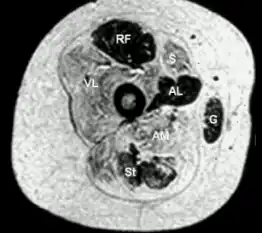

Transverse section from child with central core disease

The diagnosis is made based on the combination of typical symptoms and the appearance on biopsy (tissue sample) from muscle. The name derives from the typical appearance of the biopsy on light microscopy, where the muscle cells have cores that are devoid of mitochondria and specific enzymes.[2]